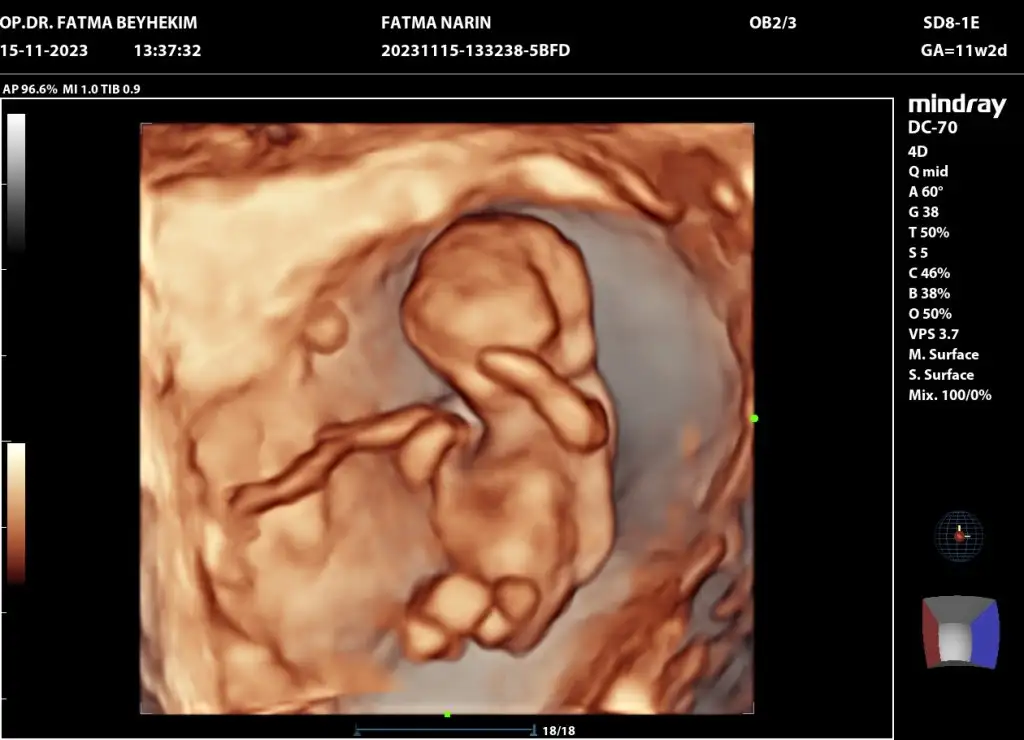

11 haftlik halii erkek demisdin dha beli deil doktor tahminm var dedi ama erkn 2 hafta sonra kesin soyliycm sna dedi 3 aylik olucaz .. erkn ogrncem cinsyti acaba erkek oldu icin mi erkn . Digr kizlrm 5 ve 6 ayda beliydiBu kesinlikle erkek

Valla ben bilmem. Anlamam da. Ama çok erken. 17.haftaya kadar kız dediler sonra erkek oldu bizim. Kim ne derse desin inanmayın.11 hafta simdi sizce nedr

Anldmm tskr .. canm doktr da bana iki hafta sonra gel dedi kesin soylicem dedi . 11 haftyz suan acaba bukdr erkn soylemsi erkek olablrmi kizlrin gec belli oluyoValla ben bilmem. Anlamam da. Ama çok erken. 17.haftaya kadar kız dediler sonra erkek oldu bizim. Kim ne derse desin inanmayın.

Evet o zaman erkek görmüş olabilir ama sadece tahmin. Bizim oğluşun pipisi gözükmedi 17 ye kadar. 2 hafta sonra söylemesi de çok güvenli olmaz ama renkli ultrasonu varsa kesin görürAnldmm tskr .. canm doktr da bana iki hafta sonra gel dedi kesin soylicem dedi . 11 haftyz suan acaba bukdr erkn soylemsi erkek olablrmi kizlrin gec belli oluyo